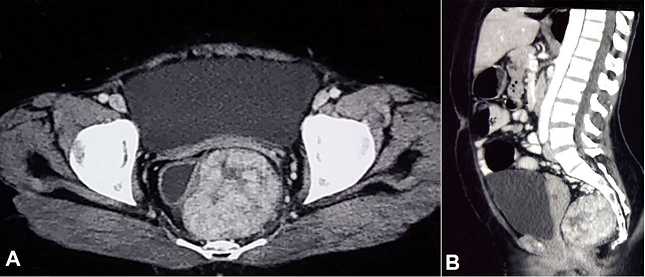

A 30-year-old female presented complaining of dysmenorrhea for 1 year. She had normal bladder and bowel habits. A pelvic examination revealed an extra-rectal mass on the right para-rectal space, pushing the uterus towards the left side. The rectal mucosa was normal. Contrast-enhanced computed tomography of the abdomen and pelvis showed the presence of a well-defined mass with heterogenous contrast-enhancement in the left presacral area abutting the left lateral wall of the rectum ( Figure 1).

Our imaging finding of a well-defined mass with heterogeneous contrast enhancement and many surrounding dilated vessels is similar to other published reports 8,11 ( Figure 1). This may be considered as a common imaging feature of PHAT. The presence of high-density areas on non-contrast computed tomography (CT), which did not show any enhancement, was probably due to hemorrhage within the lesion, and was confirmed by the histopathologic study.